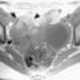

Struma ovarii

A struma ovarii (literally: goitre of the ovary) is a rare form of monodermal teratoma that contains mostly thyroid tissue, which may cause hyperthyroidism.Despite its name, struma ovarii is not restricted to the ovary. The vast majority of struma ovarii are benign tumours; however, malignant tumours of this type are found in a small percentage of cases. [Source: Wikipedia ]